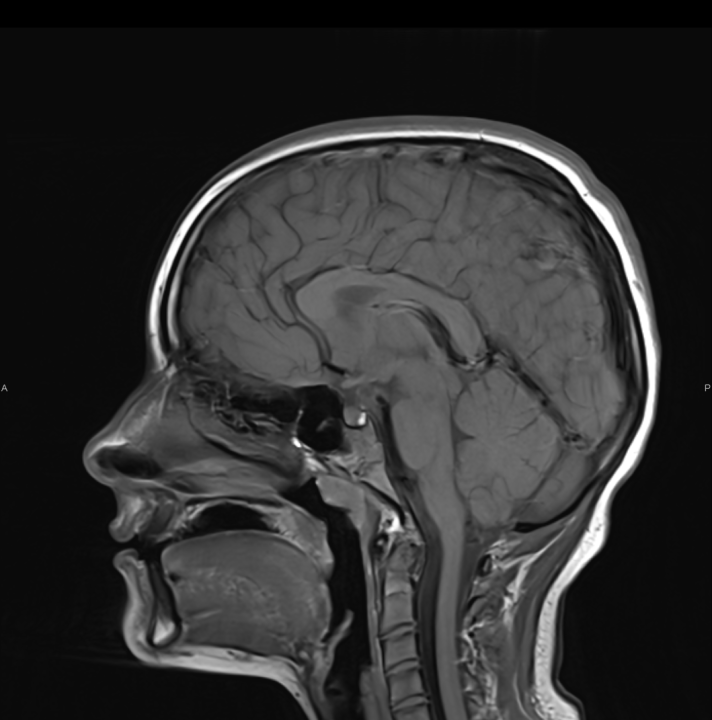

Tijekom Tjedna mozga Poliklinika Affidea Vita daje 20 posto popusta na magnetsku rezonancu!

Povodom obilježavanja Tjedna mozga od 11.

tjedan mozga

MR mozga

MR angiografija